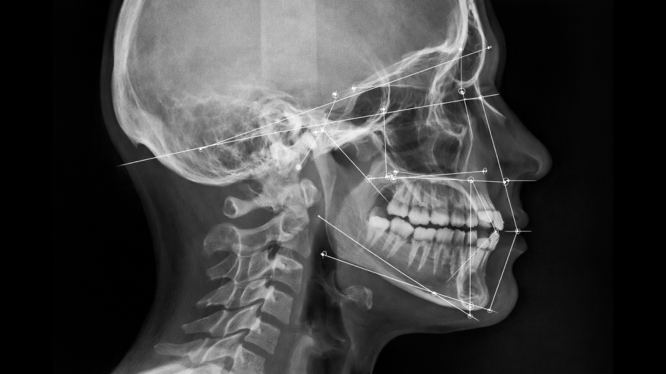

La cefalometría es un estudio radiográfico especializado que analiza la relación entre los huesos del cráneo, la mandíbula, los dientes y los tejidos blandos del rostro.

Es una radiografía lateral del cráneo que permite medir, evaluar y diagnosticar cómo está estructurada tu cara y tu sonrisa.

El especialista realiza un análisis cefalométrico, que incluye:

📐 Mediciones precisas:

- Ángulos óseos

- Distancias entre estructuras

- Posición dental

- Relación maxilar-mandíbula

🧠 Interpretación clínica:

- Tipo de crecimiento facial

- Diagnóstico ortodóncico

- Plan de tratamiento personalizado